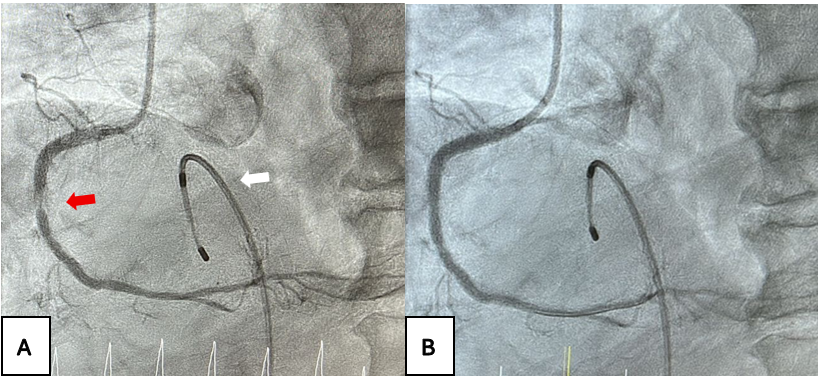

Four hours later, the IABP alarm sounded because of failure to inflate, raising suspicion of balloon rupture attributable to aortic calcification. Emergency IABP removal was planned. A long wire (0.025-inch × 175-cm J-wire) was inserted through the IABP lumen. Standard balloon aspiration was attempted prior to removal, but resistance was encountered when withdrawing the IABP from the arteriotomy site. Clot formation within the balloon likely caused bulging, preventing extraction (Figure 2A).

To address this, the 8F sheath was withdrawn over the wire, and its tip was cut 1 cm longitudinally to create a flared end. The flared sheath was then carefully readvanced into the femoral artery lumen via the arteriotomy. This maneuver smoothed out the bulging IABP balloon, enabling complete removal of the system (Figures 2B and 3). Given the anticipated arteriotomy size exceeding 8F post-removal, a 14F MANTA vascular closure device (Teleflex) was deployed, successfully closing the wound. The vascular surgery team remained on standby throughout for potential open surgical bailout in case percutaneous removal failed.